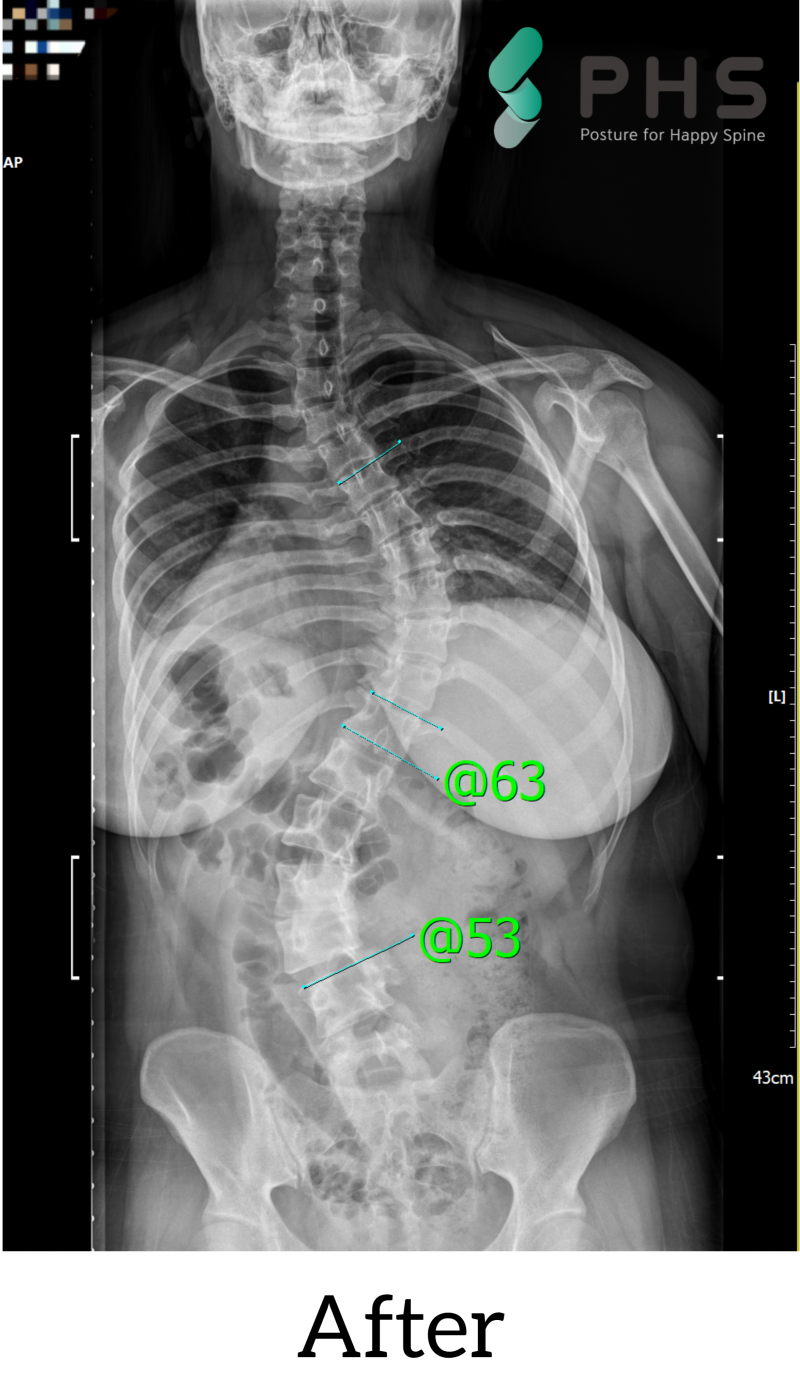

척추측만증 10대 청소년 척추측만증 70도->63도 개선

척추측만증 70도->63도